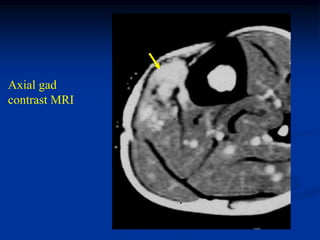

Case #1204

22 year male with

hemangioma anterior

compartment leg with

subadjacent cortical

hypertrophy of tibia

Axial gad

contrast MRI

Coronal T-1 MRI